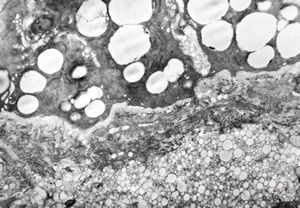

Whipple disease - lipid malabsorption

jejunum … lipid malabsorption